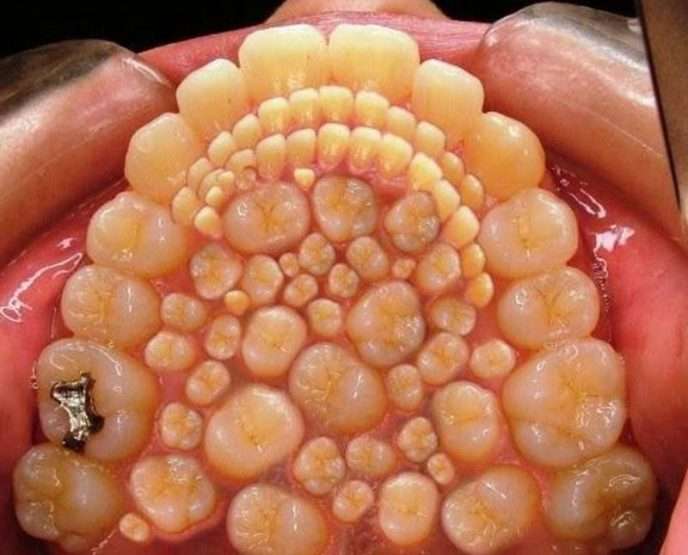

Այս լուսանկարները կարող են ապշեցնել յուրաքանչյուրին։ Արդյո՞ք սա ֆոտոշոփ է։ Ահա թե այս լուսանկարներից որոնք են իրական, իսկ որոնք են ֆոտոշոփի մասնագետի աշխատանք։